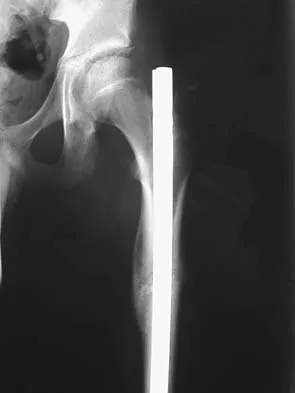

Figure 7 shows the AP radiograph of a 60-year-old man who has had pain in the thigh for past 6 months. History reveals that he underwent hip replacement 1 year ago. The radiographic changes are most likely the result of what process?

Explanation

The arrows in the radiograph point to circumferential radiolucencies that strongly support the diagnosis of septic loosening. Radiolucent lines that occur in such a short time are also typical of an infection. Garvin KL, Hanssen AD: Infection after total hip arthroplasty: Past, present, and future. J Bone Joint Surg Am 1995;77:1576-1588.